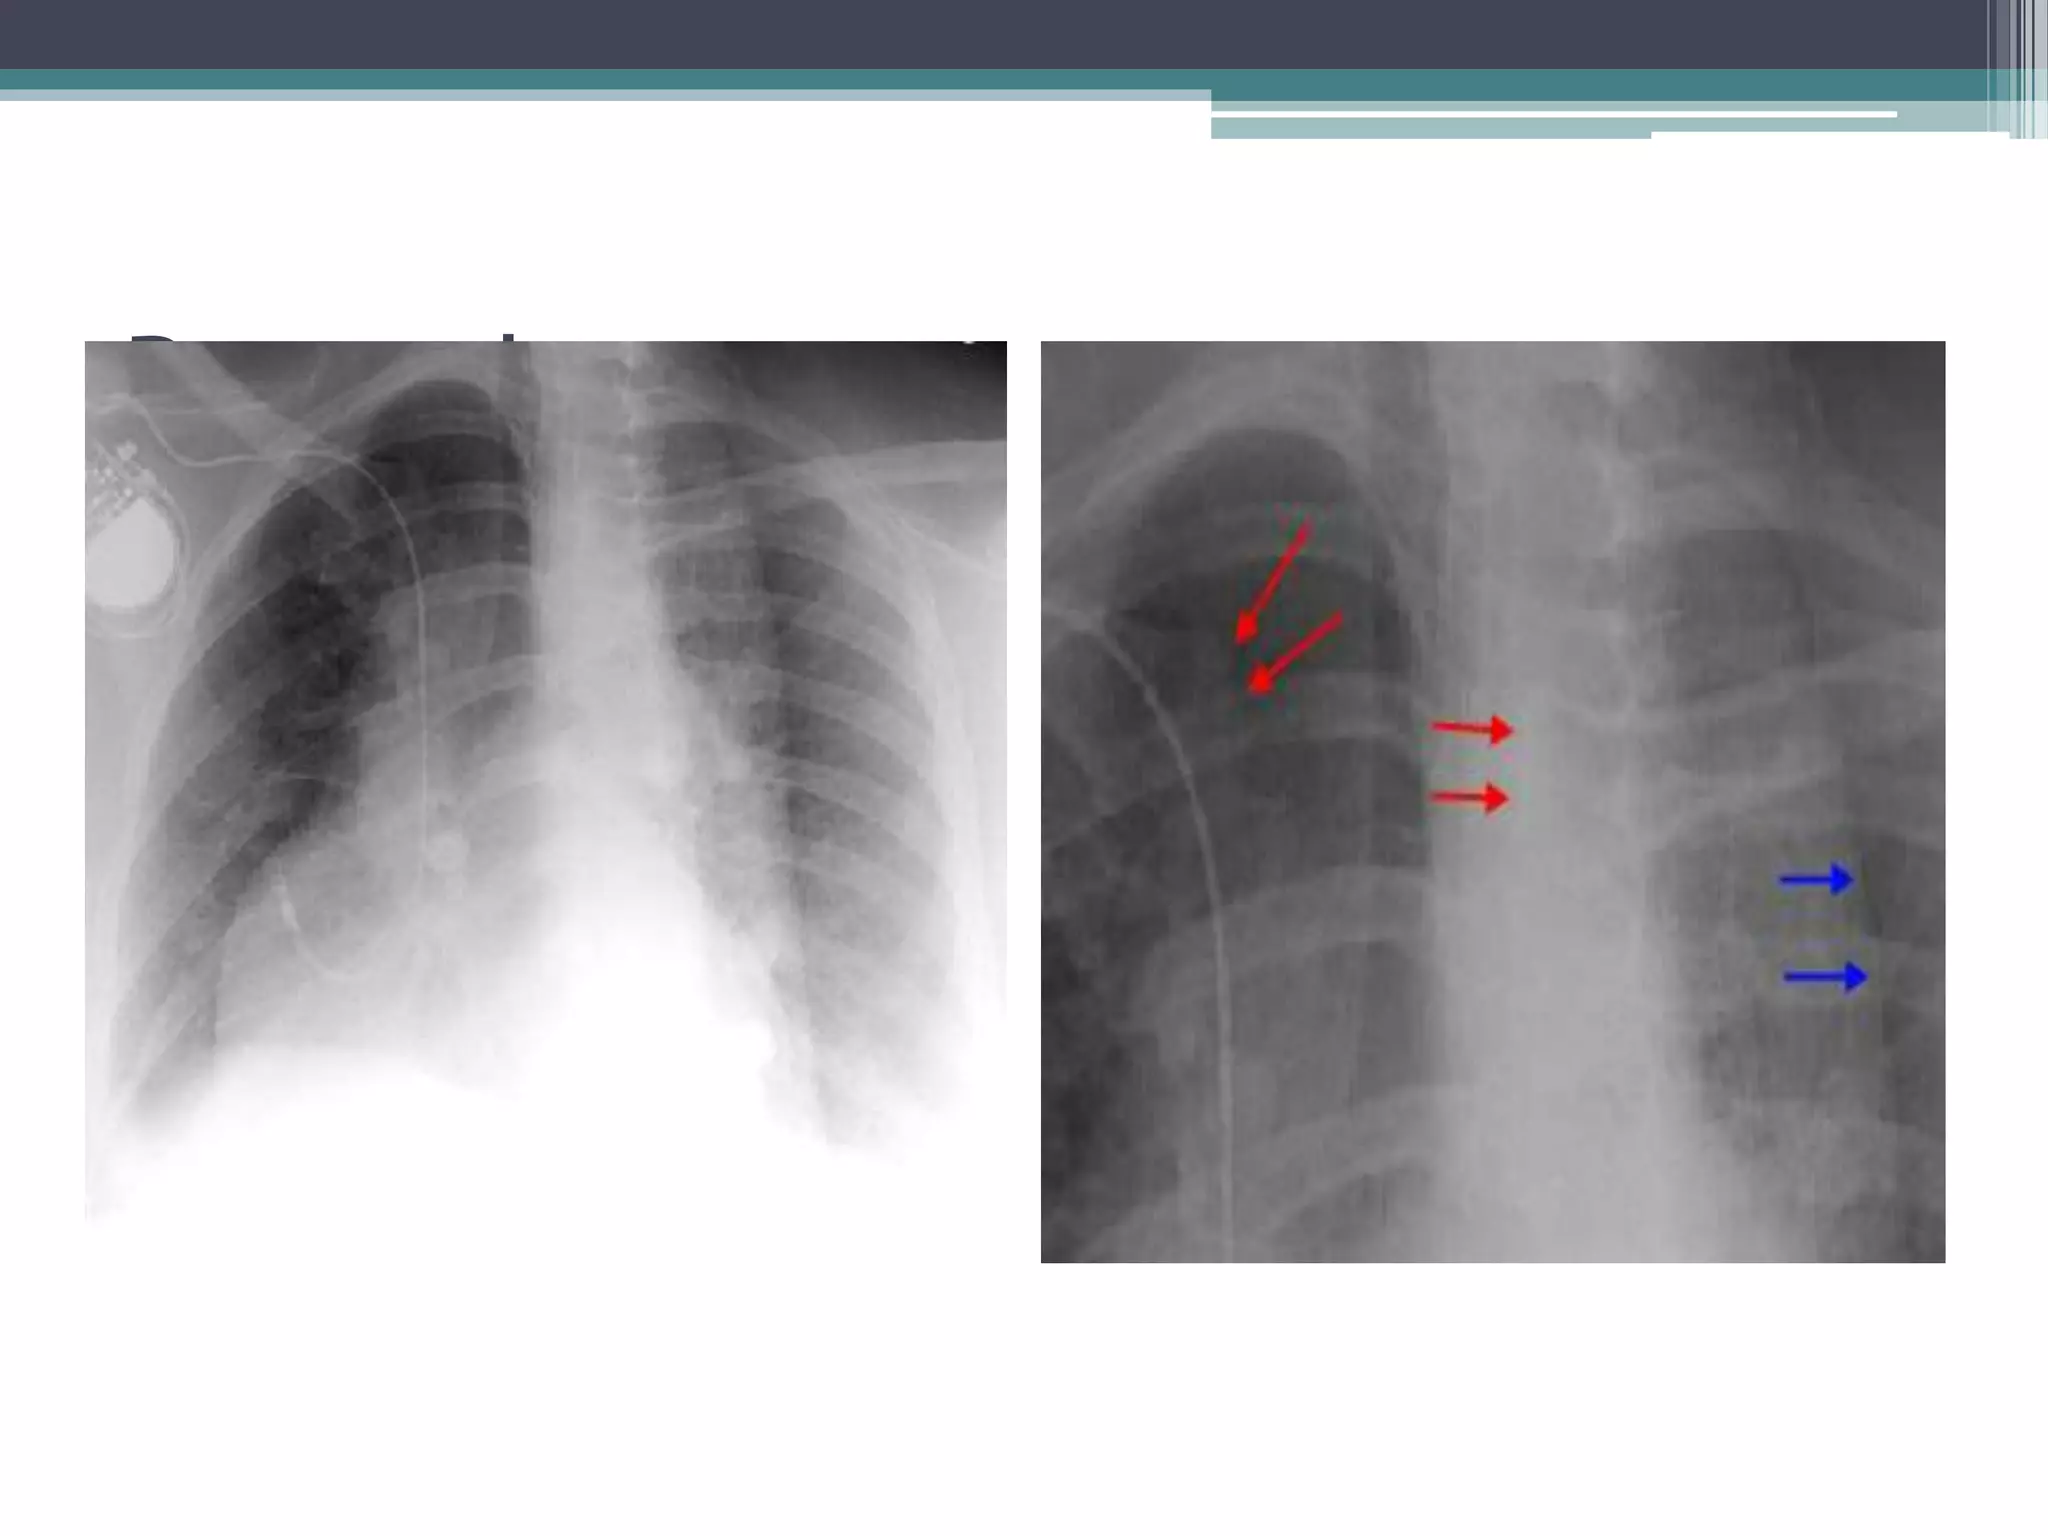

Chest Radiography Positioning Pdf Position of patient standing erect – left or right (usually left lateral is shown). the patient should be leaning slightly forward with the shoulder resting firmly against the grid. Always perform chest imaging sitting or standing, whenever possible. in an upright position the diaphragm will move farther down on inspiration, allowing the lungs to fully aerate. an upright position will also demonstrate any possible air fluid levels in the pleural cavity. Whenever possible the patient should be imaged in an upright pa position. ap views are less useful and should be reserved for very ill patients who cannot stand erect. 5) rotation in chest x rays rotation means the patient isn’t positioned straight. this can make anatomy look shifted or distorted, which may be mistaken for disease.

Chest X Ray Positioning Whenever possible the patient should be imaged in an upright pa position. ap views are less useful and should be reserved for very ill patients who cannot stand erect. 5) rotation in chest x rays rotation means the patient isn’t positioned straight. this can make anatomy look shifted or distorted, which may be mistaken for disease. The document outlines the positioning considerations and radiation protection techniques for chest radiography, emphasizing the importance of accurate central ray location and collimation to minimize patient exposure. 1. 14 x 17 film 2. patient is in a recumbent lateral position (side down as ordered). 3. have patient raise arms out of chest area. 4. 72" sid 5. central ray: perpendicular to film. 6. deep inspiration expiration patient positioned the same as pa chest except exposure is made on complete expiration. 45 degree lao and 45 degree rao 1. 14 x 17. A good quality chest x ray is a must to detect chest diseases. a proper x ray is correctly centred and taken with the correct exposure factors while the patient holds breath in deep inspiration. Both the image receptor and x ray tube should be perpendicular to each other. this is more easily achievable when a patient is in a true erect or supine position and more difficult when the patient is recumbent.